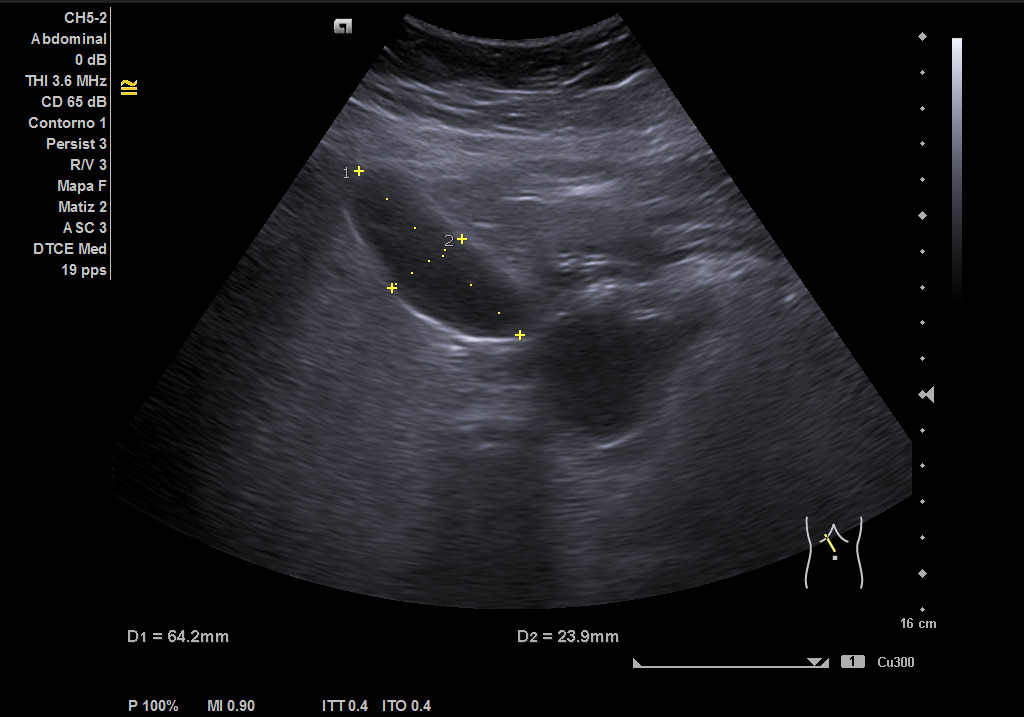

Ecografía clínica: hígado de tamaño y contornos conservados, con aumento difuso de la ecogenicidad, sin presencia de lesiones focales en las porciones visualizadas. Vesícula biliar alitiásica de tamaño y paredes normales. Vía biliar no dilatada. Imagen redondeada de 36,5 mm hipoecoica homogénea que muestra flujo con el Doppler que corresponde con porta extrahepática. Páncreas parcialmente visualizado sin alteraciones valorables. Bazo de tamaño conservado. Ambos riñones normoposicionados, de tamaño y grosor cortical conservados con buena diferenciación corticosinusal. Vejiga replecionada de paredes lisas. No líquido libre intrabdominal. Imagen redondeada de 36,5 mm hipoecoica homogénea que muestra flujo con el Doppler que corresponde con porta extrahepática. Conclusión: esteatosis hepática grado II, imagen redondeada de 36.5mm hipoecoica homogénea que muestra flujo con el Doppler que corresponde con porta extrahepática.

Ecografía: esteatosis hepática moderada e imagen altamente sugestiva de aneurisma de la vena porta extrahepática, permeable y de unos 39 mm aproximadamente.

Aneurisma de vena porta extrahepática.

La ecografía clínica nos ha servido para detectar un hallazgo muy poco frecuente (el aneurisma de Porta supone un 3% de todos los aneurismas venosos) y cuyo manejo no está claro. Su detección puede contribuir a incrementar el conocimiento sobre el mismo.